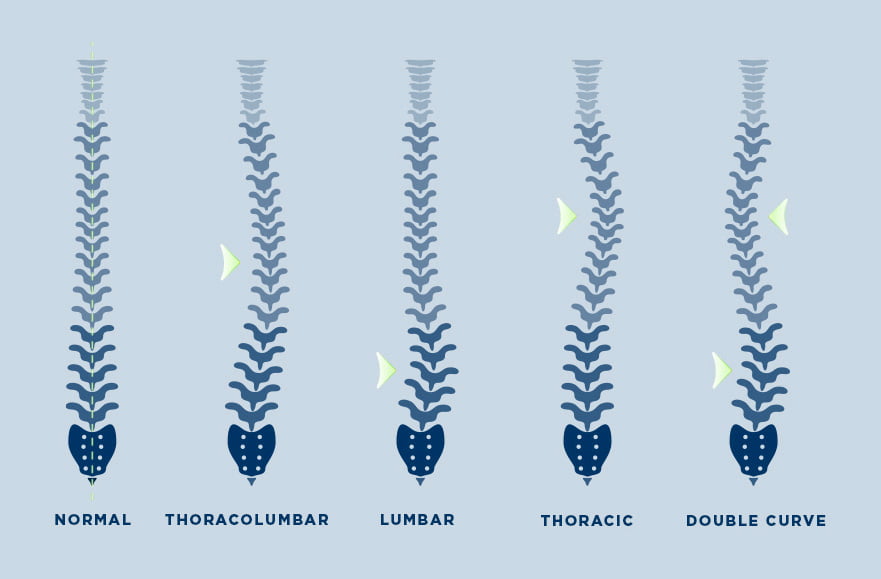

تصنيف منحنيات الجنف Classification of scoliosis curves

كل منحنى جنف فريد من نوعه. قد ينحني العمود الفقري إلى اليسار أو اليمين ويمكن أن يحدث في أجزاء مختلفة من العمود الفقري. إذا كان في منطقة الصدر يسمى الجنف "الصدري"، بينما إذا كان في الجزء السفلي من العمود الفقري يسمى الجنف "القطني". ومن الممكن أيضًا أن يكون هناك منحنيان؛ وهذا ما يسمى انحناء مزدوج وقد يبدو العمود الفقري على شكل حرف "S" من الخلف. ومن الممكن أيضًا الحصول على المزيد من المنحنيات التعويضية في أعلى وأسفل العمود الفقري. نظرًا لأن الجنف هو حالة ثلاثية الأبعاد ويحاول العمود الفقري دائمًا التعويض، فهناك العديد من الاختلافات المحتملة في المنحنيات. ومع ذلك، فإن المنحنى الأكثر شيوعًا هو المنحنى الصدري الأيمن.